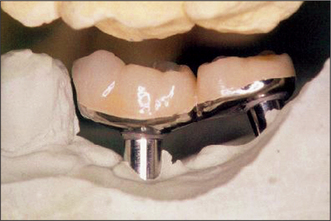

PROSTHODONTIC REHABILITATION AFTER IMPLANT SURGERY

Prosthodontic rehabilitation typically involves the use of ball attachments, magnets, a retentive bar with clips to support an overdenture, or the construction of a fixed prosthesis (e.g. a crown or bridge as seen in Fig. 11.32). Further discussion of the methods employed may be obtained from a suitable textbook on dental prosthetics.

Fig. 11.32 The fixed prosthesis with the free-end saddle fabricated for the patient in Figs 11.27-11.31.